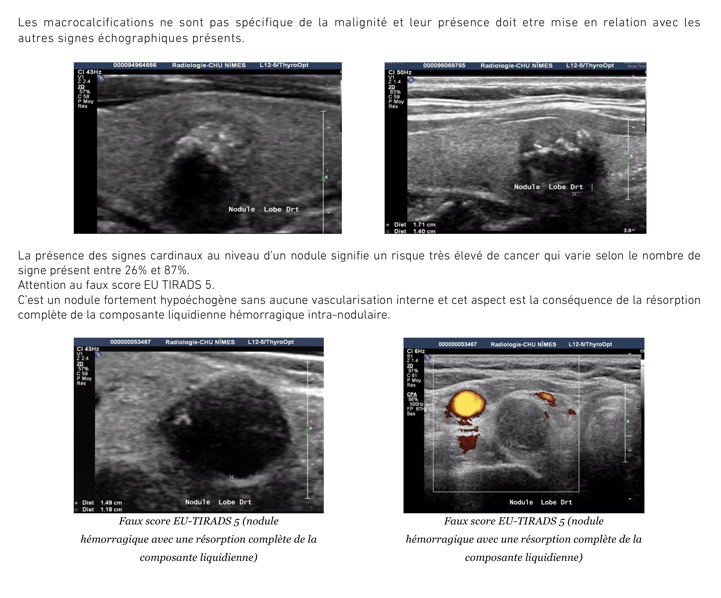

Se méfier des formations hypoéchogènes